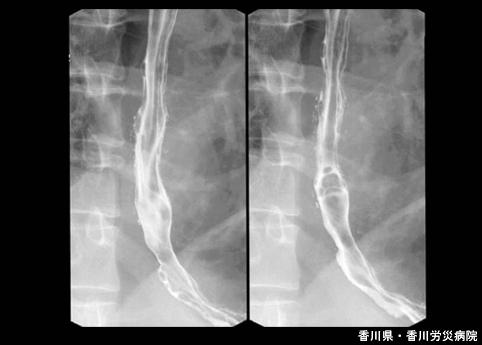

칸디다에 의한 식도위게실 (증례제시:카가와현, 카가와산업재해병원, Dr카게야마, 코지마)

[Image-ID:5081]

염증성 및 궤양성질환/칸디다 식도염

식도/2개 이상

X-P